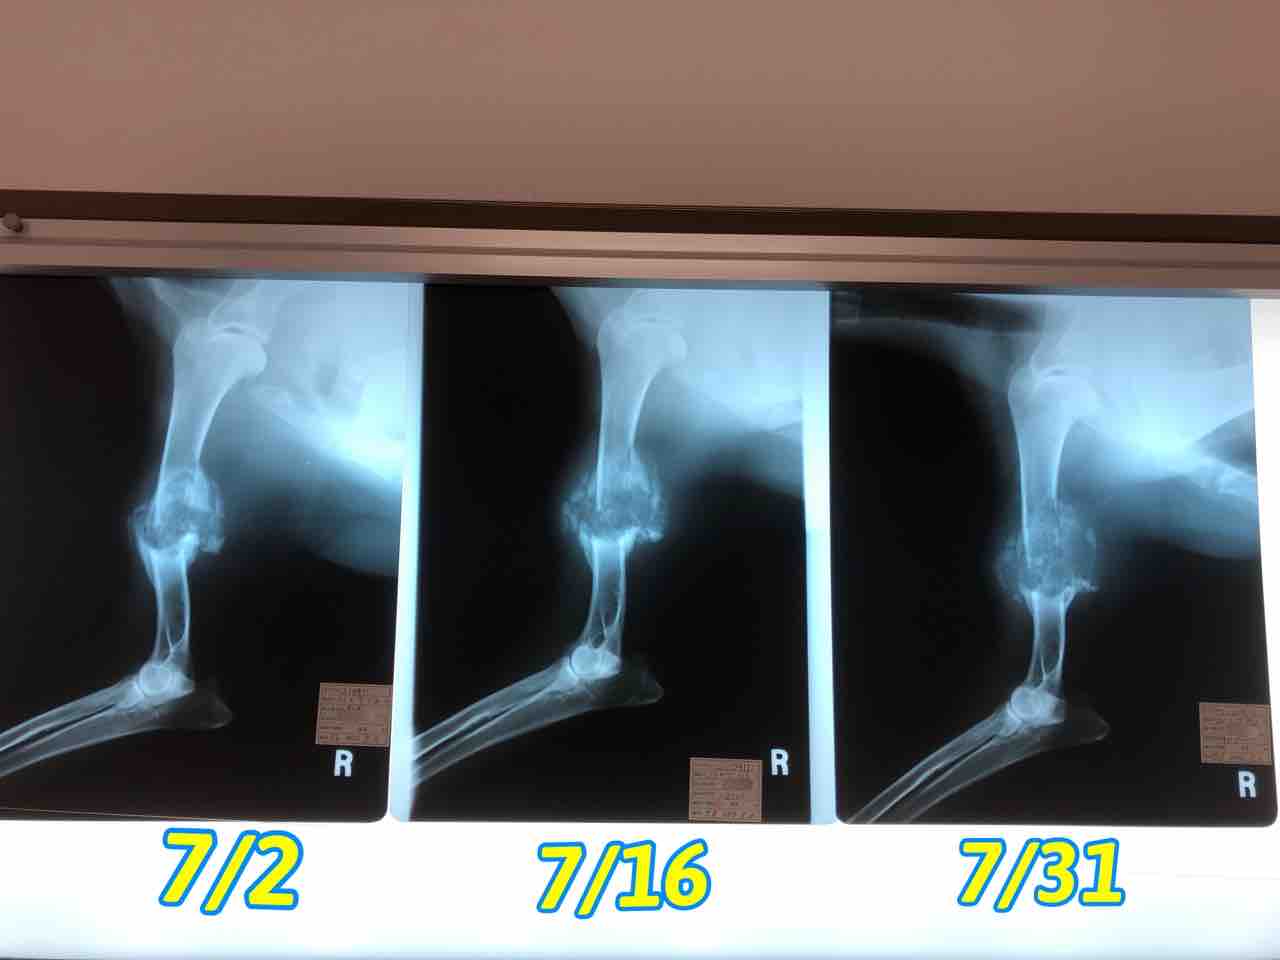

右後ろ脚

早く使えるようになるといいな〜

右前脚は全く使えずブラブラ…

この↑腫瘍が悪さをしてるのかな

骨が溶けて折れてるから…痛いよねー